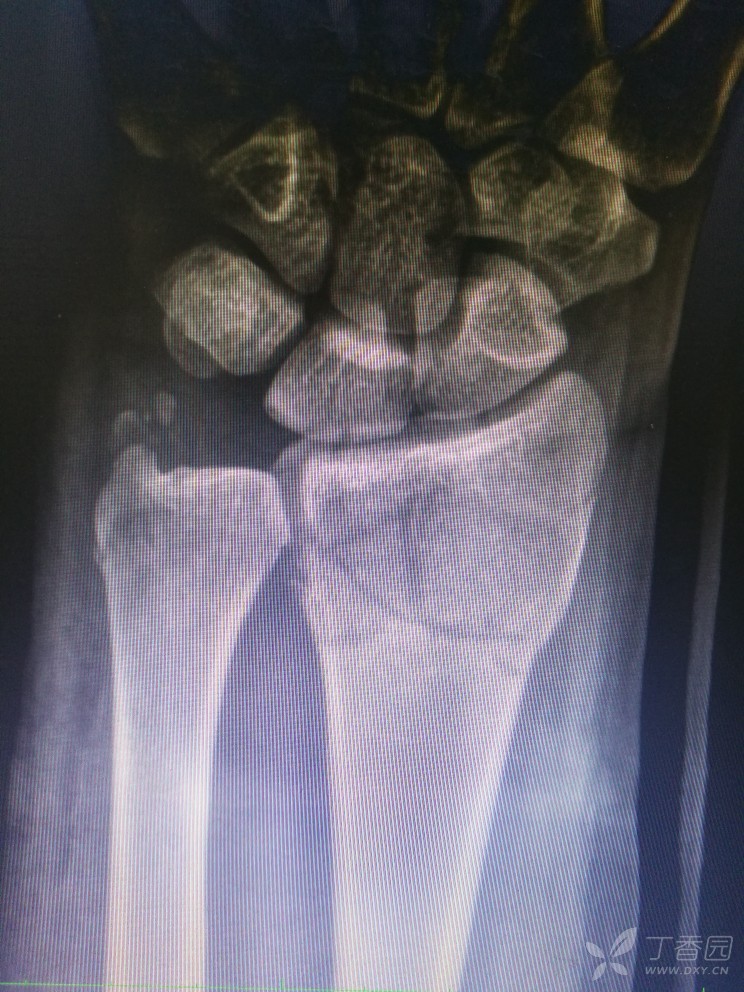

柯氏骨折

图片尺寸1040x780